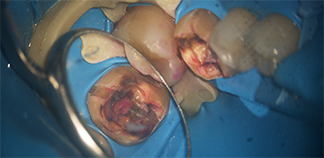

До лечения

Жалобы на разрушенный зуб.

Пациенту 35 лет.

Как лечили

Был удален шестой разрушенный зуб. На его место пересажен восьмой зуб. Через 2 недели проведено эндодонтическое лечение. Изготовлена и установлена коронка на восьмой зуб.

Лечение проведено в течение двух недель.